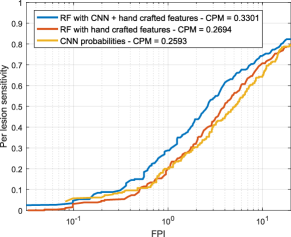

Free-response ROC (FROC) curves were used to evaluate the performance of our red lesion detection method on a per lesion basis. These plots, which are extensively used in the literature to estimate the overall performance on this task, represent the per lesion sensitivity against the average number of false positive detections per image (FPI) obtained on the data set for different thresholds applied to the candidate probabilities. Thus, FROC curves provide a graphical representation of how the model is able to deal with the detection of true lesions in all the images of the data set. We also computed the Competition Metric (CPM) as proposed in the Retinopathy Online Challenge (Niemeijer et al., 2010), which is the average per lesion sensitivity at the reference FPI values . The protocol used by Seoud et al. (2016) was followed when evaluating in DIARETDB1, as indicated in Section 3.1.

Experiment 2 was carried out on e-ophtha to estimate the ability of our method to segment MAs and smaller HEs simultaneously. In this case, a combination of both the DIARETDB1 (MA labels with a level of agreement ) and ROC training sets was used for learning, as we observed that few MAs (only 182 for the entire DIARETDB1 set) are retrieved at agreement. To the best of our knowledge, the only method evaluated on e-ophtha is by Wu et al. (2017), although their analysis is performed on a subsample of 74 images with lesions instead of the full data set. By contrast, we used a more challenging evaluation comprising the entire e-ophtha set, including also the 233 images with no visible sign of DR. Figure 9 presents the FROC curves obtained using each approach. As in the previous experiment, the Wilcoxon signed rank tests showed a statistical significant improvement in the per lesion sensitivity values using the hybrid vector of both deep learned features and domain knowledge with respect to the CNN probabilities and the hand crafted features ( and , respectively).

Table 5 summarizes the CPM values obtained for each experiment and each feature combination, and also using each of the two recently published state-of-the-art methods. Per lesion sensitivities at FPI, which is considered a clinically relevant number of false positives (Niemeijer et al., 2010) are also provided.

When analyzing each individual characterization approach, it is possible to see in Experiment 1 that both the RF trained with hand crafted features and the CNN achieved higher per lesion sensitivities than the method by Seoud et al. (2016) ( and , respectively). This is likely due to the fact that our method for extracting candidates differs from the one used by the alternative approach. Moreover, Seoud et al. (2016) eliminate the lesion candidates occurring within an estimated area around the optic disc center, which is determined using an automated approach. As a consequence, if the diameter of the optic disc is accidentally overestimated by such a method, candidates within valid regions will be suppressed and it will not be possible to recover them afterwards during the classification stage. As seen in Figures 14 and 15, our combined approach is able to discriminate the candidates within the optic disc area and the vascular structures. Hence, instead of using a rigid elimination step based on optic disc segmentation, we let the classifier to decide whether a candidate is actually a true positive or a false positive occurring on an anatomical region. This approach increases the maximum achievable per lesion sensitivity on each image, allowing to train our classifier with a larger amount of false positive lesions and to get a higher sensitivity in test time. A similar observation can be made from the results of Experiment 2, in which the hand crafted features and the deep learning based approach reported higher per lesion sensitivities than those reported by Wu et al. (2017). It must be underlined, also, that the Wu et al. (2017) method was trained on the first half of the images with pathologies on e-ophtha and evaluated on the second half, rather than trained on a separate data set and evaluated on the complete set, as in our case. Moreover, it is worth noting that the images of the healthy patients were also included during evaluation to get a more accurate estimation of its actual performance on a real, clinical scenario.